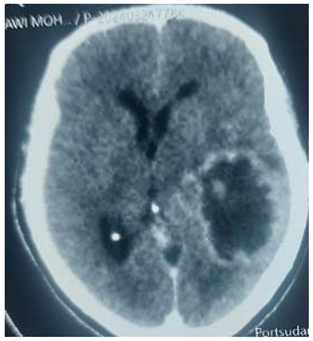

Preprints 114904 i004

An urgent VP shunt anterior approach was done, after which the patient showed improvement concerning headache, but few weeks followed he developed unsteady gait and dizziness

When we counseled the patient and his family, the decision of surgery was made and the patient was prepared for excision of the cyst.

Operation: Through Rt para median craniectomy, intra operative; there was cyst containing oily like fluid and soft tissue, thus macroscopic excision was done.

Histopathology

Showed low grade oligodendroglioma.

Patient discharge home in a good condition, but presented with superficial wound infection consequently debridement was done.